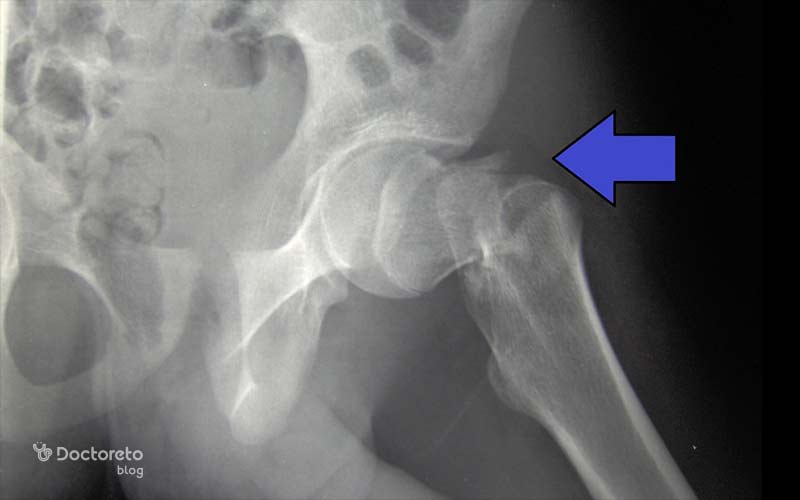

عکس پوکی استخوان لگن و ران

برای تشخیص و بررسی پوکی استخوان در لگن و ران، از روشهای مختلف تصویربرداری امآرآی، پزشکی هستهای و رادیوگرافی ساده استفاده میشود. در هر یک از این روشها، شاخصههای مختلفی ارزیابی میشوند. بهعنوانمثال MRI در پوکی استخوان اولیه جایگزینی پراکنده مغز استخوان با چربی را نشان میدهد؛ ادم و خطوط شکستگی بیشتر در شکستگیهای ثانویه دیده میشود.

خطوط شکستگیهای زیر غضروفی نیز در این تصاویر مشخص است. تصاویر MRI در افراد مبتلا به پوکی استخوان، تصویر واضحی از بافت نرم اطراف لگن، مانند ماهیچهها و تاندونها را نیز ارائه میدهد.